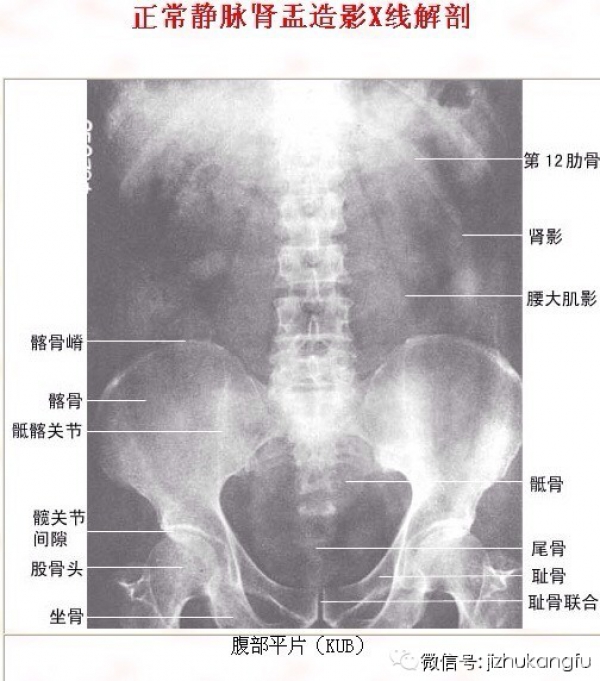

2颈椎

4内脏器官

2脊柱